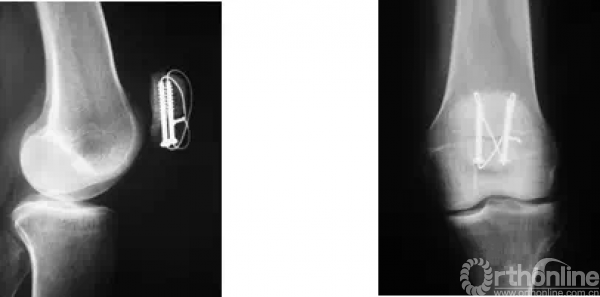

术前X线,下级粉碎,中下段上下分层。

采用纵向切口,术中探查,下极十分粉碎无法修复,采用两枚铆钉置入中断骨折断端

将缝线沿髌骨下极两侧腱膜出缝出,然后缝两个loop后互相打结

用巾钳加持复位,透视下见复位满意

从髌骨下极行空心螺钉贯穿到髌骨上极固定

透视见导针位置满意

拧入适当长度的空心螺钉

用钛缆环扎固定

用缝线加固腱膜层,冲洗缝合伤口,术后照片